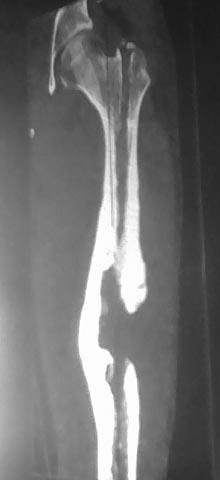

На снимках осложнение огнестрельного перелома бедра поздней инфекцией. 7 лет назад оперирован: правое бедро, сперва на ExFix, затем заменен на гвоздь, а левая - гвоздь при поступлении.

Беспокойство проявил недавно, по поводу жалоб на боли сделано МРТ и дренирование абсцесса терапевтами. Мы удалили гвоздь, сделали I&D, рассверливание канала, и ввели гвоздь с антибиотиком. Для гвоздя использовали стерильную трубку-форму, а антибиотик по 1.0 Tobramycin c Vancomycin.

В замкнутом без перелома пространстве во время риминга повышается давление внутри канала, и имеется риск тромбообразования. Для профилактики и для дренажа - каннюлированный винт 6.5 мм в дистальной части бедра. Обработку заканчивают культурой из раны и канала. Иногда процедуру надо будет повторить.

Рекомендуется: антибиотический гвоздь на цементе. Нагрузку можно разрешить сразу, перелом сросся давно!